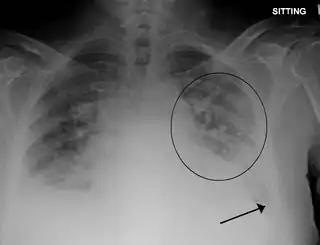

Radiografía de tórax con edema pulmonar y pequeños derrames pleurales bilaterales

• Una radiografía de tórax que puede revelar líquido en o alrededor del espacio pulmonar o un agrandamiento del corazón.